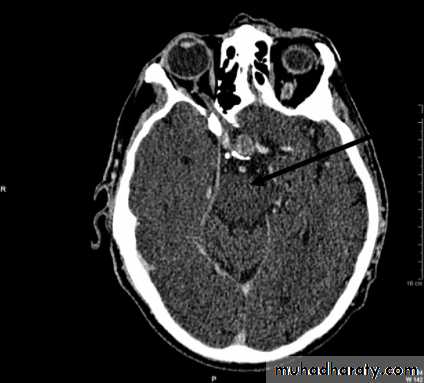

• Computed Tomography scan (CT scan) with/without contrast• Magnetic Resonance Imaging (MRI) with/without contrast